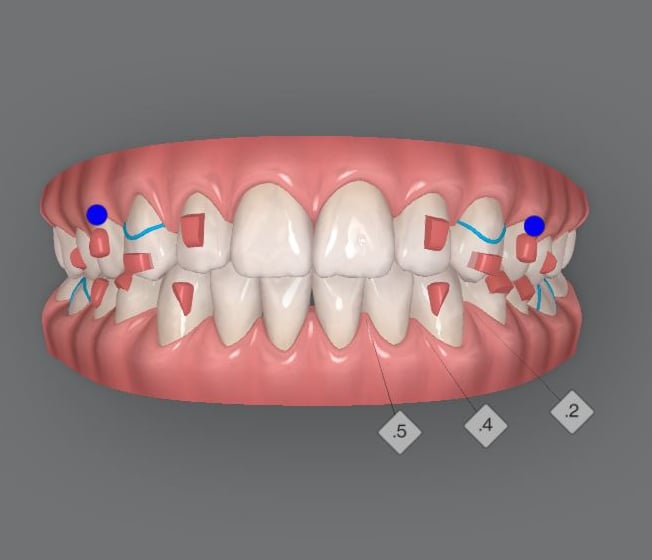

Teeth Crowding

Experience the transformative power of Shrine's Invismile in addressing teeth crowding. Our specialized techniques ensure precise alignment, unveiling a confident and beautifully corrected smile. Say goodbye to crowding with Shrine's Invismile.